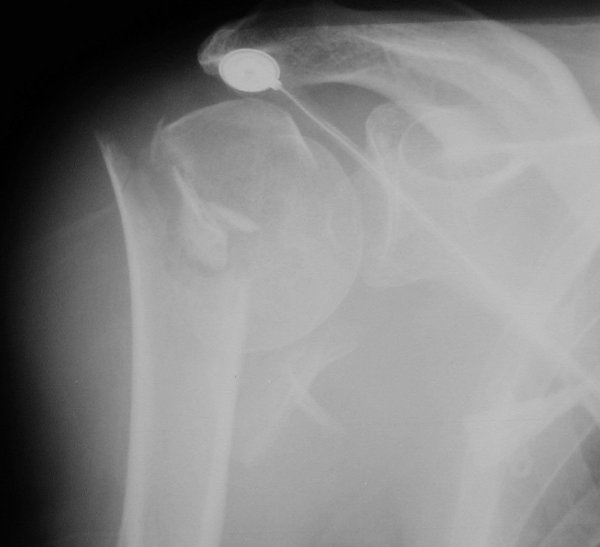

Return to Proximal Humerus Fracture